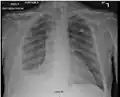

There are three key elements to the diagnosis of silicosis. First, the patient history should reveal exposure to sufficient silica dust to cause this illness. Second, chest imaging (usually chest x-ray) that reveals findings consistent with silicosis. Third, there are no underlying illnesses that are more likely to be causing the abnormalities. Physical examination is usually unremarkable unless there is complicated disease. The examination findings are not specific for silicosis.[20]

For uncomplicated silicosis, chest x-ray will confirm the presence of small (< 10 mm) nodules in the lungs, especially in the upper lung zones. Using the ILO classification system, these are of profusion 1/0 or greater and shape/size "p", "q", or "r". Lung zone involvement and profusion increases with disease progression. In advanced cases of silicosis, large opacity (> 1 cm) occurs from coalescence of small opacities, particularly in the upper lung zones.

With retraction of the lung tissue, there is compensatory emphysema. Enlargement of the hilum is common with chronic and accelerated silicosis. In about 5–10% of cases, the nodes will calcify circumferentially, producing so-called "eggshell" calcification. This finding is not pathognomonic (diagnostic) of silicosis. In some cases, the pulmonary nodules may also become calcified.

- Chest X-ray showing uncomplicated silicosis